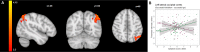

While impaired response inhibition has been reported in attention-deficit/hyperactivity disorder (ADHD), findings in disruptive behavior disorders (DBDs) have been inconsistent, probably due to unaccounted effects of co-occurring ADHD in DBD. This study investigated the associations of behavioral and neural correlates of response inhibition with DBD and ADHD symptom severity, covarying for each other in a dimensional approach. Functional magnetic resonance imaging data were available for 35 children and adolescents with DBDs (8-18 years old, 19 males), and 31 age-matched unaffected controls (18 males) while performing a performance-adjusted stop-signal task. No significant association was found between behavioral performance and symptom severities. However, contrasting successful inhibition with failed inhibition revealed that DBD and ADHD symptom severity was associated with greater activation in the right inferior frontal regions and reduced activation in the bilateral striatal regions, respectively. During successful inhibition versus go-trials, ADHD symptom severity was associated with the left lateral occipital cortex activation. The contrast of failed inhibition versus go-trials revealed reduced activation in the right frontal and left parietal regions associated with DBD symptom severity while ADHD symptom severity was associated with bilateral precunei, dorsolateral prefrontal and left posterior parietal regions. Except for the right inferior frontal regions during successful versus failed inhibition, all clusters were also found to be inversely associated with the other dimension of interest (i.e., DBD or ADHD symptoms). Opposite direction of the associations between DBD and ADHD symptom severity, and fronto-parietal and fronto-striatal activation suggest unique contributions of DBD and ADHD to the neural correlates of response inhibition.